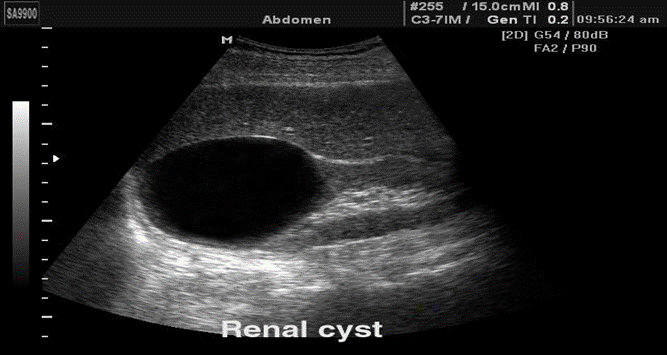

Simple cysts are very common in the middle-aged and elderly. They are filled with clear fluid with ‘acoustic enhancement’.

Most cysts are spherical in shape. They may be solitary or multiple, unilocular or have septations.

*When the ultrasonographer is sure that the diagnosis is a simple cyst, no further investigation is needed. *

Simple cyst in kidney on u/s and CT